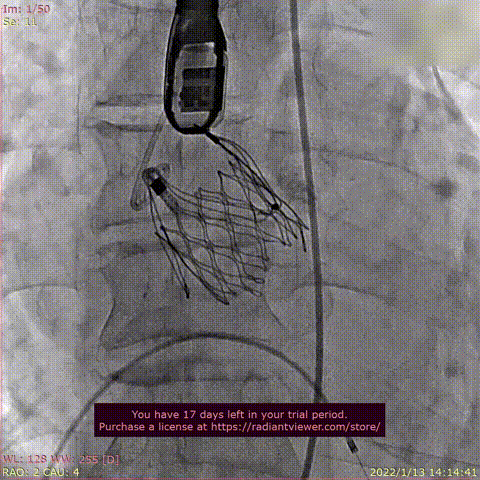

患者为68岁男性,因“活动后心累,气紧半年,加重1周“主诉入院。术前超声提示全心增大,左室肥厚,LVDD 75mm ,LVEF 48%,主动脉瓣重度反流。术后即刻主动脉瓣大量反流消失,LVDD 59mm,左室较术前显著缩小。

瓣膜释放过程